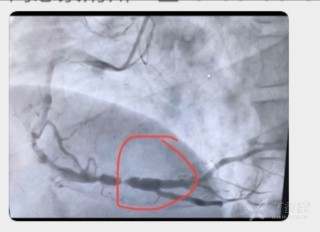

3时10分血压升至161/108mmHg,多巴胺逐渐减至1ml/h,与家属沟通后,3时25分由120绿色通道转至上级医院行急诊pcI治疗。治疗过程中,发现右冠后三叉狭窄后扩张直径>5.5mm,支架最大4.0mm,支架不能贴壁,如下图

针对以上急诊PCI,在短时间内无法给予适合的支架时,该如何处理,谢谢各位老师给出建议